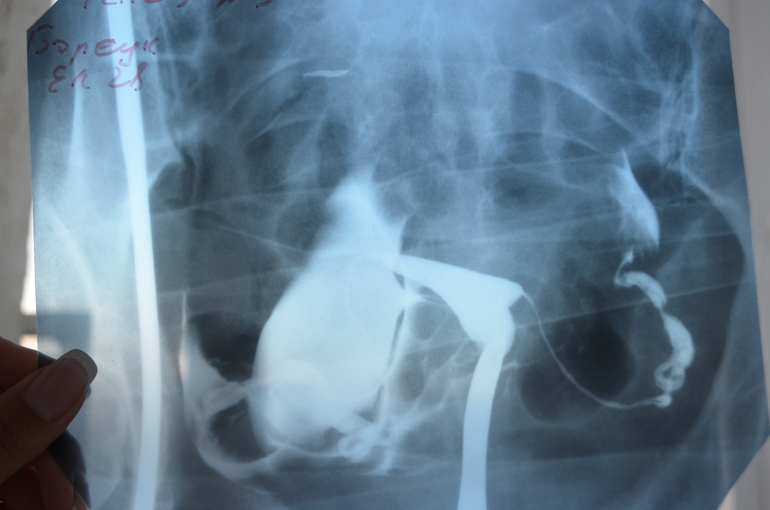

Результаты МСГ

ГСГ, ЭХО, МСГ, ФертилоскопияДевочки, как по Вашему мнению, у меня трубы проходимы? Какая вероятность забеременеть с такими трубами?

Врач ответила что трубы проходимы, но очень длинные и со спайками, настрого запретила планировать и назначила массаж(

Врач напугала, что у меня куча спаек и назначила три курса дорогостоящего массажа. Разве массаж поможет избавится от спаек?